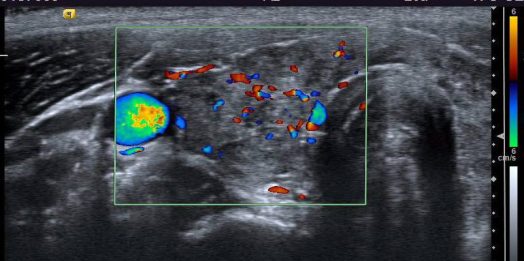

Colocaremos el doppler color para comprobar vascularización normal de la glándula y sacaremos foto si lo consideramos necesario. (recomendado).

In this image 1 we look for a global visualization of the gland and we are interested in the echographic aspect of both lobes. Next to the left lobe we observe the visible portion of the esophagus. We will place the color Doppler to check normal vascularization of the gland and we will take a photo if we consider it necessary. (recommended).

Comprobación doppler